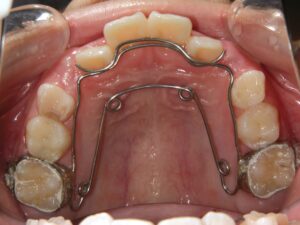

使用装置

緩徐拡大装置(クワドヘリックス)

前歯部ブラケット

第2期治療開始時

口腔内写真

開始年齢

13歳